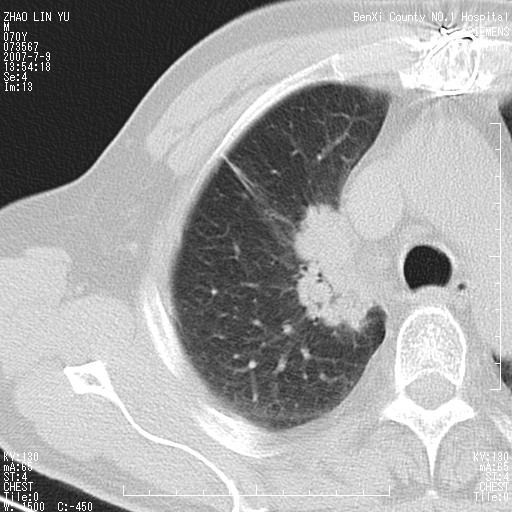

以下是引用王靖旗在2007-7-10 17:12:00的发言:[br] 男、70、咳嗽两个月,半年前换瓣手术,胸片未见异常,于昨天行x片发现右肺上野大片影,行ct扫描,这里是减薄图像,余肺正常。明天晚上会有增强扫描片,到时我会上传。[br][br] 冠状位请大家细看,应该是有意义的,[br][br] 请大家先看平扫发表意见。[br][br]

以下是引用zhangzhongshou在2007-7-10 21:43:00的发言:[br]右肺上叶周围型肺癌,以孤立型细支气管肺泡癌可能性大。